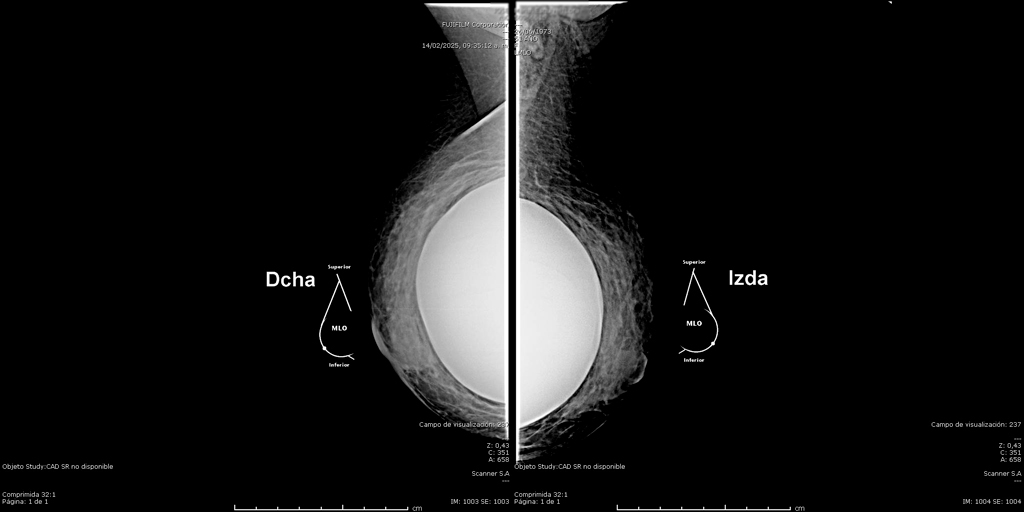

La mamografía es un estudio de diagnóstico por imagen que utiliza bajas dosis de rayos X para obtener imágenes detalladas del tejido mamario. Es una herramienta fundamental para la detección temprana del cáncer de mama y otras patologías mamarias, incluso antes de que sean evidentes al tacto o generen síntomas. Su uso regular en controles preventivos permite salvar vidas al facilitar diagnósticos oportunos y tratamientos más efectivos.

En SCANNER S.A, nuestros equipos digitalizados permiten detectar cambios mínimos en el tejido mamario con alta claridad, permitiendo asi tener un diagnostico preciso y entregar unos resultados reales a nuestros pacientes.